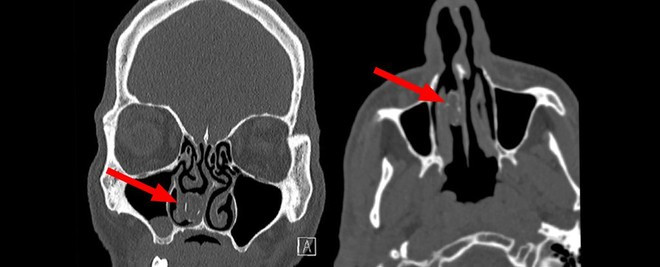

Gói cần sa kẹt trong khoang mũi người đàn ông Australia.

Khi quét vùng mũi, các bác sĩ phát hiện “một khối cứng màu xám” trong khoang mũi của người đàn ông. Các chuyên gia tai mũi họng tại Bệnh viện Westmead (Sydney) thực hiện nội soi gây mê để loại bỏ nó và lôi ra một “viên nang cao su có chứa rau/cây thoái hóa".

18 năm sau, ông giúp các bác sĩ tạo ra ca mổ đầu tiên trên thế giới để lấy một vật thể dài 1,9 cm từ khoang mũi với tên kỹ thuật là rhinolith (tiếng Hy Lạp nghĩa là đá mũi).